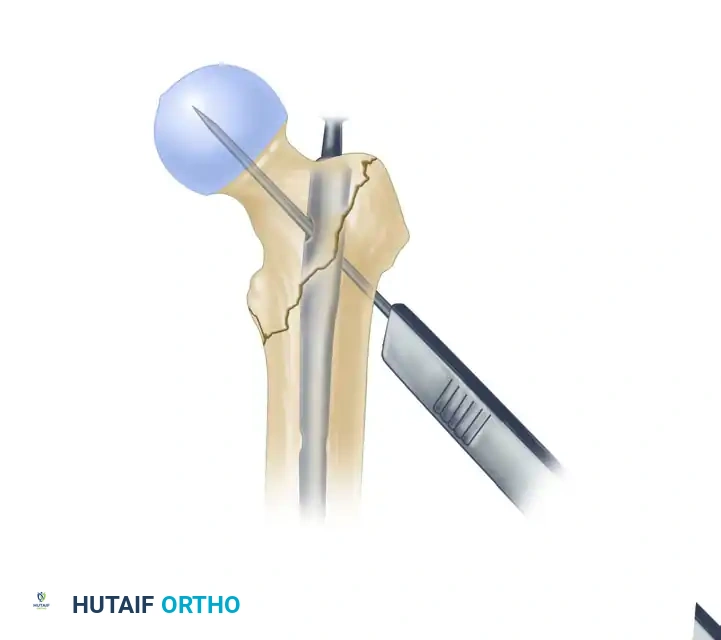

Placement of the 3.2-mm guide pin in the ideal center-center position within the femoral head, stopping 5 mm short of the subchondral bone.

- Pilot Hole and Guide Pin Placement: Use the 4.0-mm drill to create a pilot hole through the lateral cortex. Insert the 3.2-mm guide pin through the sleeve. Advance it into the femoral head.

- The goal is a center-center position: centered in the inferior half of the neck on the AP view, and perfectly centered in the head on the lateral view. Advance the pin to within 5 mm of the subchondral bone.

- Measure for the length of the lag screw using the measuring device over the guide pin. Subtract 5 to 10 mm from the measured length of the pin, depending on the amount of active compression desired.